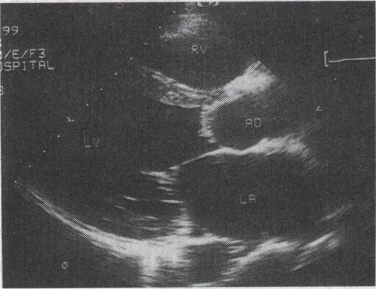

56-1. 女,28岁,停经46天,阴道不规则出血5天。血HCG68μg/ml。结合超声图像,最可能的诊断为()